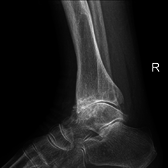

Diagnosis is made with reasonable certainty based on history and clinical examination.[42][43] X-rays may confirm the diagnosis. The typical changes seen on X-ray include: joint space narrowing, subchondral sclerosis (increased bone formation around the joint), subchondral cyst formation, and osteophytes.[44] Plain films may not correlate with the findings on physical examination or with the degree of pain.[45] Usually other imaging techniques are not necessary to clinically diagnose OA.

Severe osteoarthritis and osteopenia of the carpal joint and 1st carpometacarpel joint.

Primary osteoarthritis of the left knee. Note the osteophytes, narrowing of the joint space (arrow), and increased subchondral bone density (arrow).